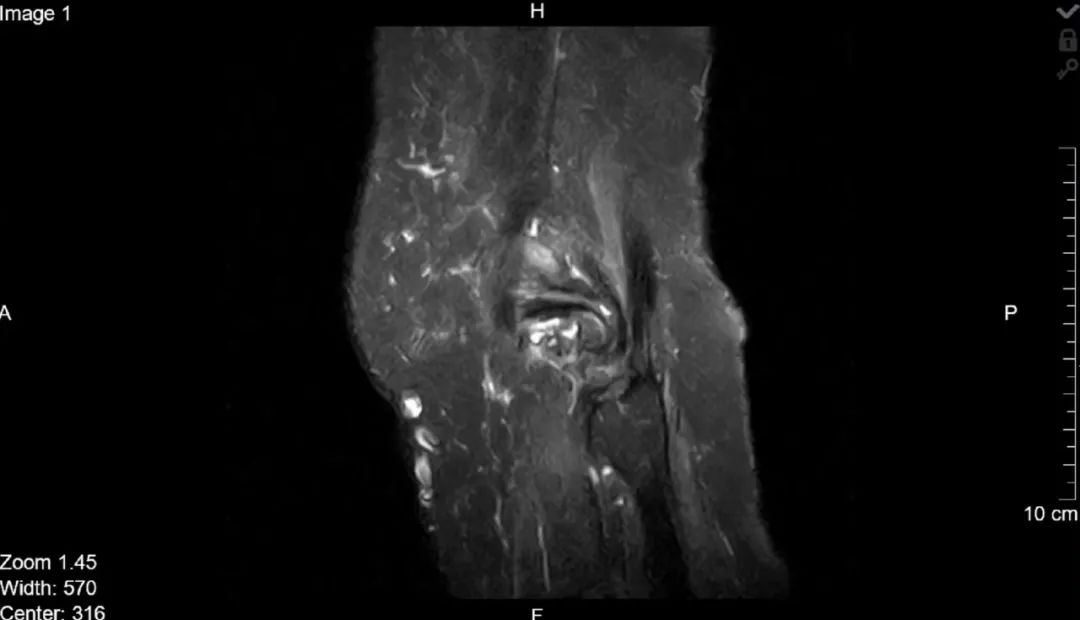

对于人体中的核磁共振成像,通常以氢核为目标,因为其中水和脂肪中有很多,然后图像的亮度基本上可以告诉我们脂肪和水的数量。人们也可以瞄准其它原子核并进行测量,这就导致了不同核磁共振图像的工作方式不同。核磁共振成像非常适合于检查软组织,而对于骨折一般则使用X射线成像。

上述提到,共振频率与磁场强度成正比,正因为如此,我们可以使用磁场梯度来瞄准特定位置的原子核,生成不同位置的身体切片图像。